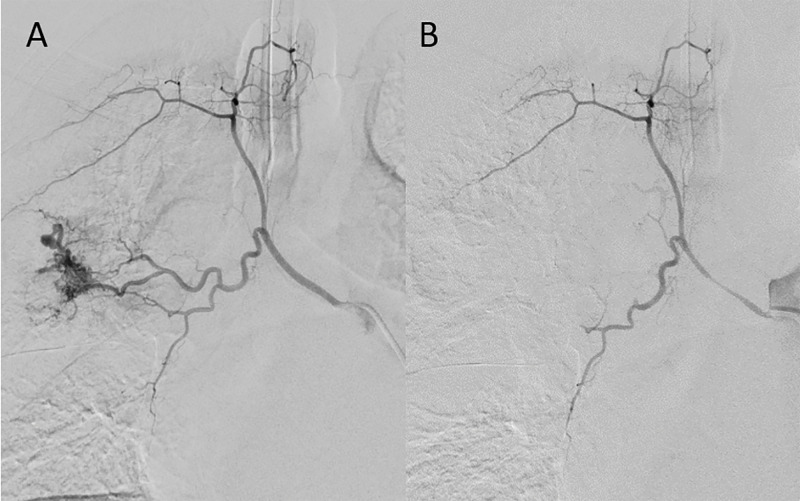

Teaching point: Pulmonary and systemic arterial phases are needed to exclude Rasmussen aneurysm.